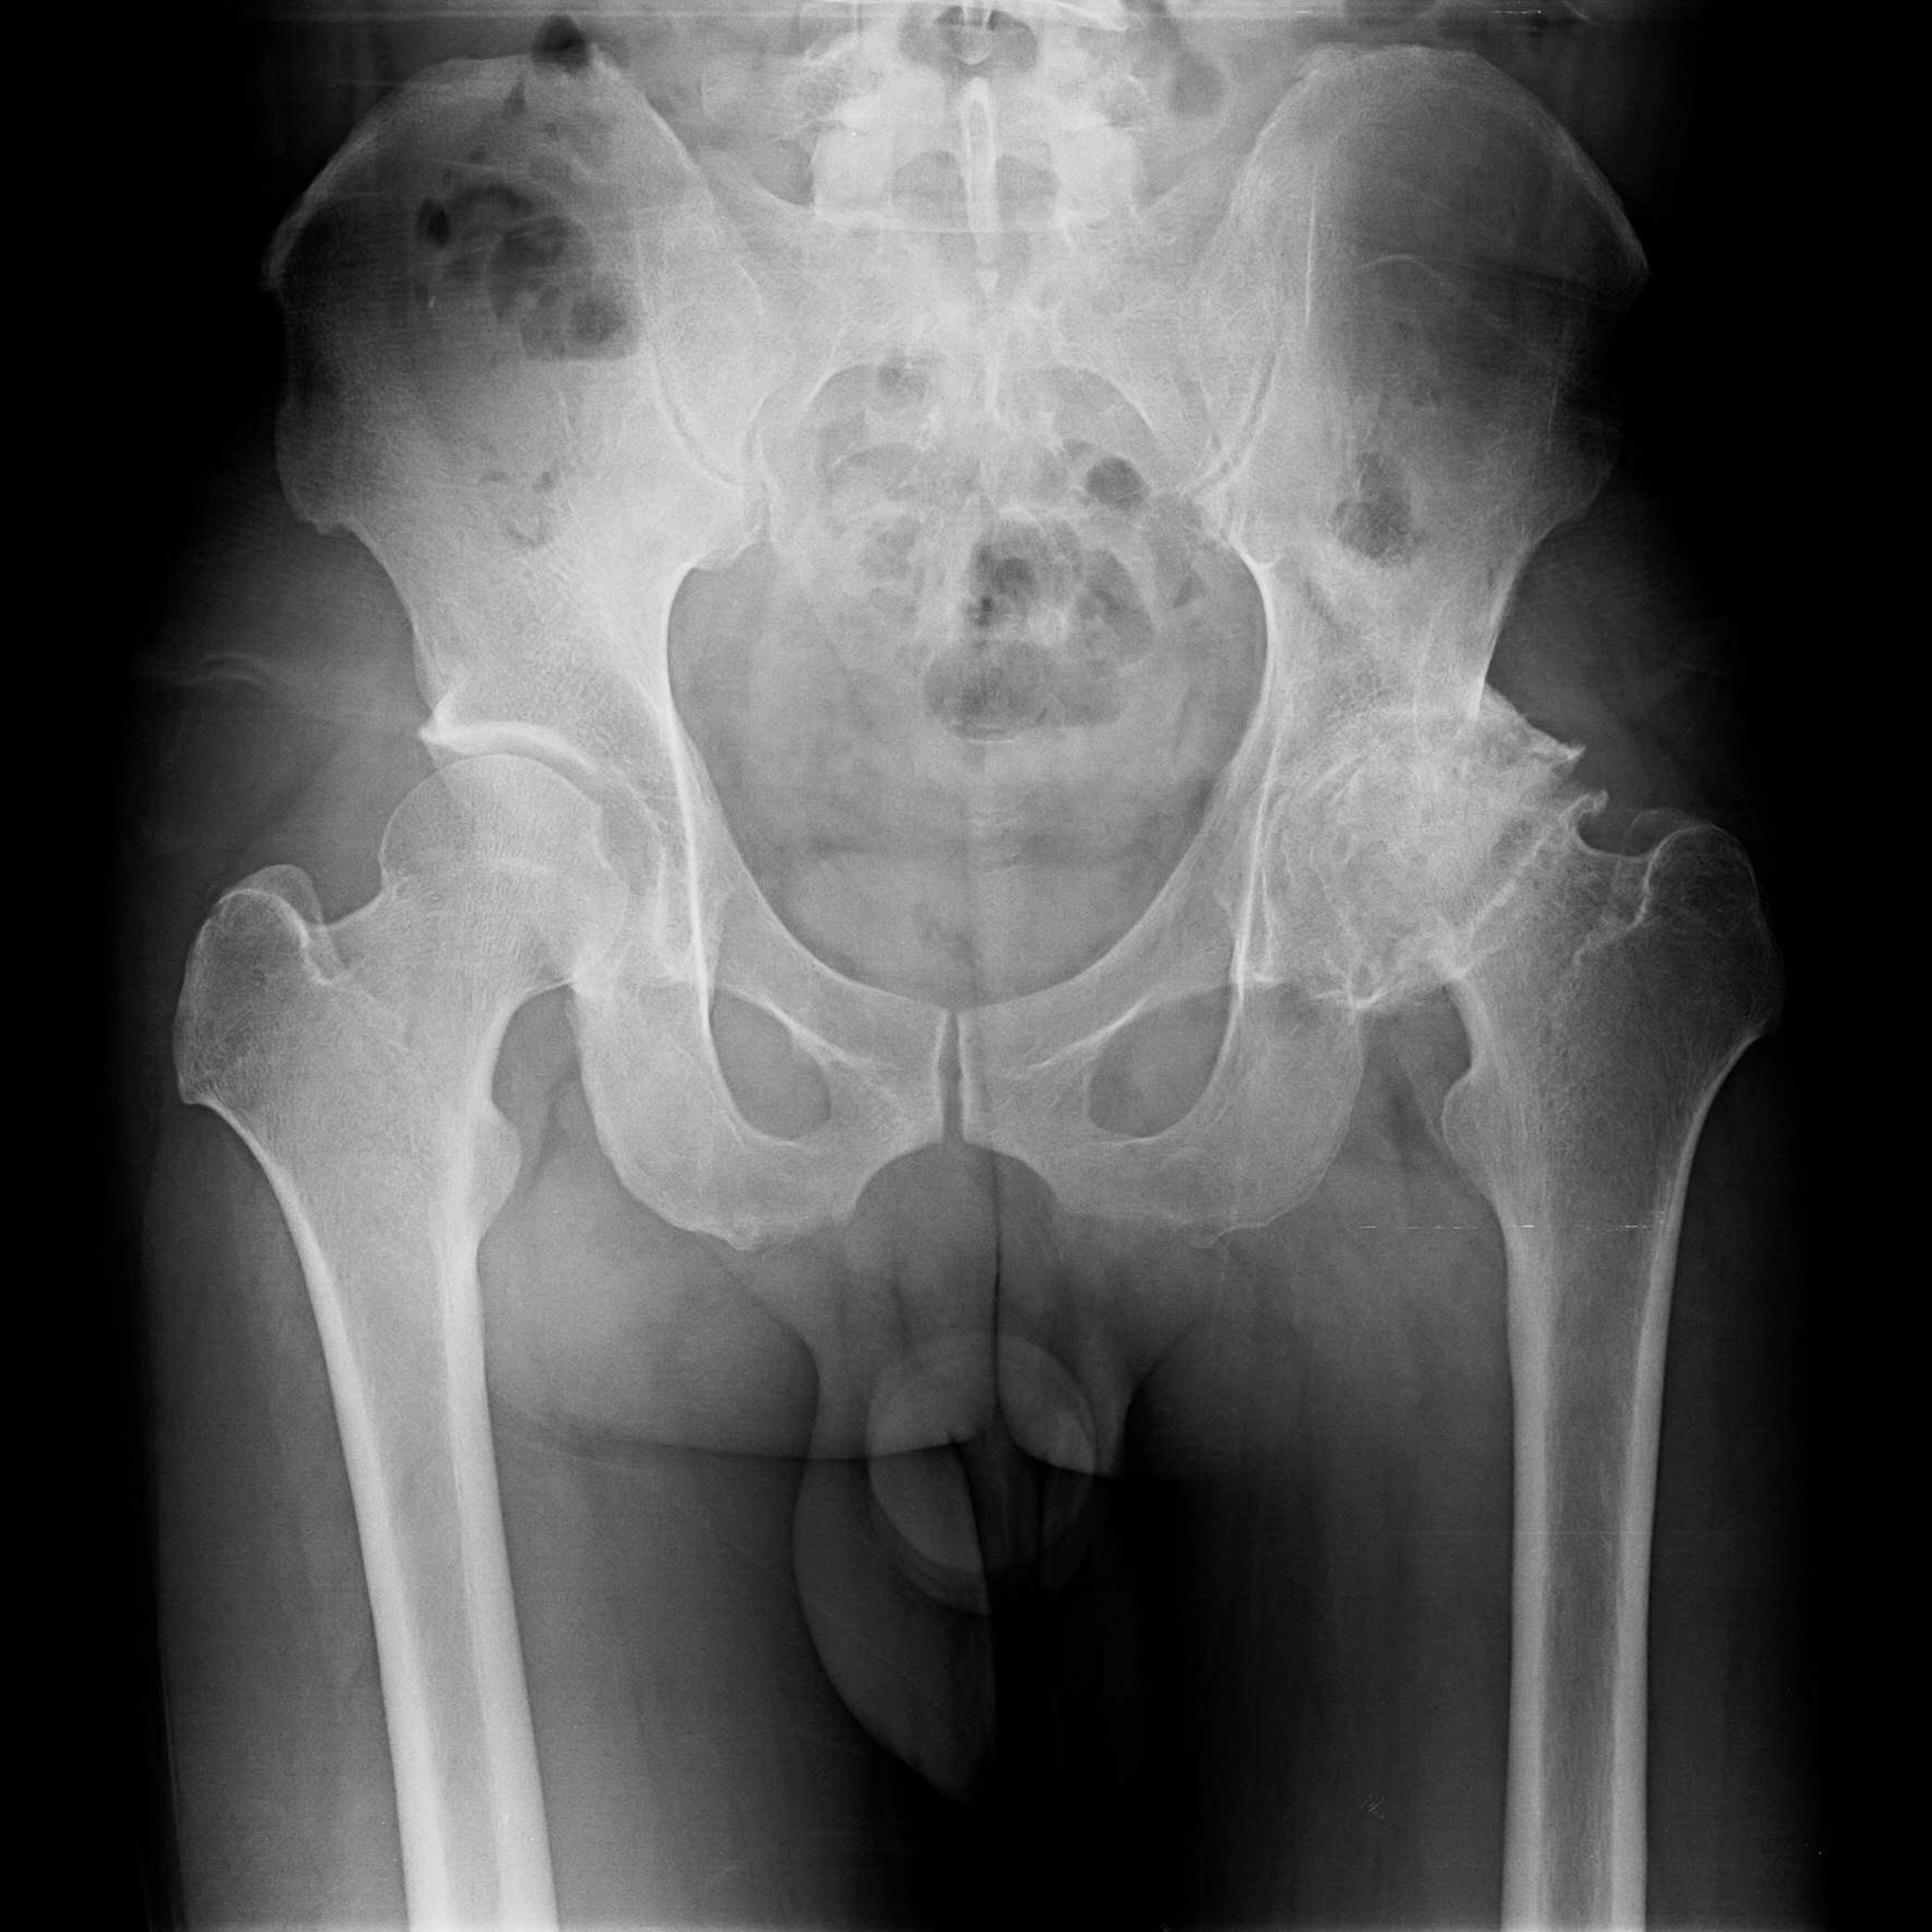

傳統髖關節置換 首頁 案例分享 髖關節手術 傳統髖關節置換 54歲蔡先生退化性關節炎 術前 術後 張女士 51歲 退化性關節炎(DDH先天發育不全 CROWE TYPE 2) 術前 術後 38歲林先生 退化性關節炎 術前 術後 72歲謝女士 退化性關節炎 術前 術後 71歲 謬女士 骨股頭壞死 術前 術後 50歲 郭先生骨股頭壞死 術前 術後 80歲 盧先生骨股頭壞死 術前 術後 林先生 37歲 術前 術後 邱女士 51歲 術前 術後 張女士 50歲 術前 術後